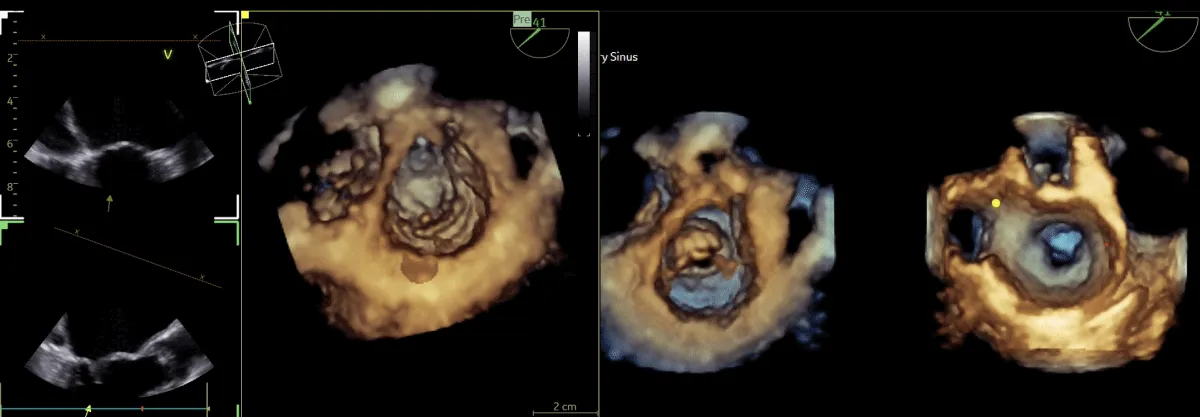

After obtaining consent, access was obtained through the right femoral vein and artery. Under 4D Transesophageal Echocardiography (4D TEE) guidance, the first transseptal puncture was performed with a broken Brough needle, and the LA wire was inserted through femoral venous access (Figure 1). Right femoral artery access was used for retrograde crossing of the aortic valve (AV) (Figure 2), and a Teflon wire was placed in the left ventricle. The aortic valve (AV) was dilated with a 14 mm ATLAS GOLD (BARD) balloon (Figure 3, Video 1).

Figure 1: A,B: 4Dimensional multiplanar transoesophageal echocardiography. A. 4D image with Left atrial wire, B. Severe mitral stenosis with mitral area of 0.5 cm2, 1C &1D. Showing multiplane of mitral valve.

Figure 2: 4Dimensional multiplanar transoesophageal echocardiography view of aortic valve.